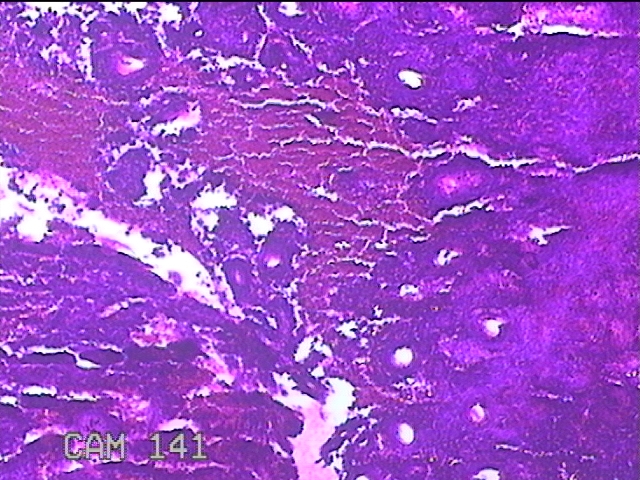

宫腔内容物

性别

女

年龄

30岁

临床诊断

1)异常子宫出血 2)子宫内膜息肉 3)宫内节育器

一般病史

间断性阴道流血后半年余。

标本名称

大体所见

灰白暗红色不规则碎组织2.5x1.8x0.8cm一堆。

图2